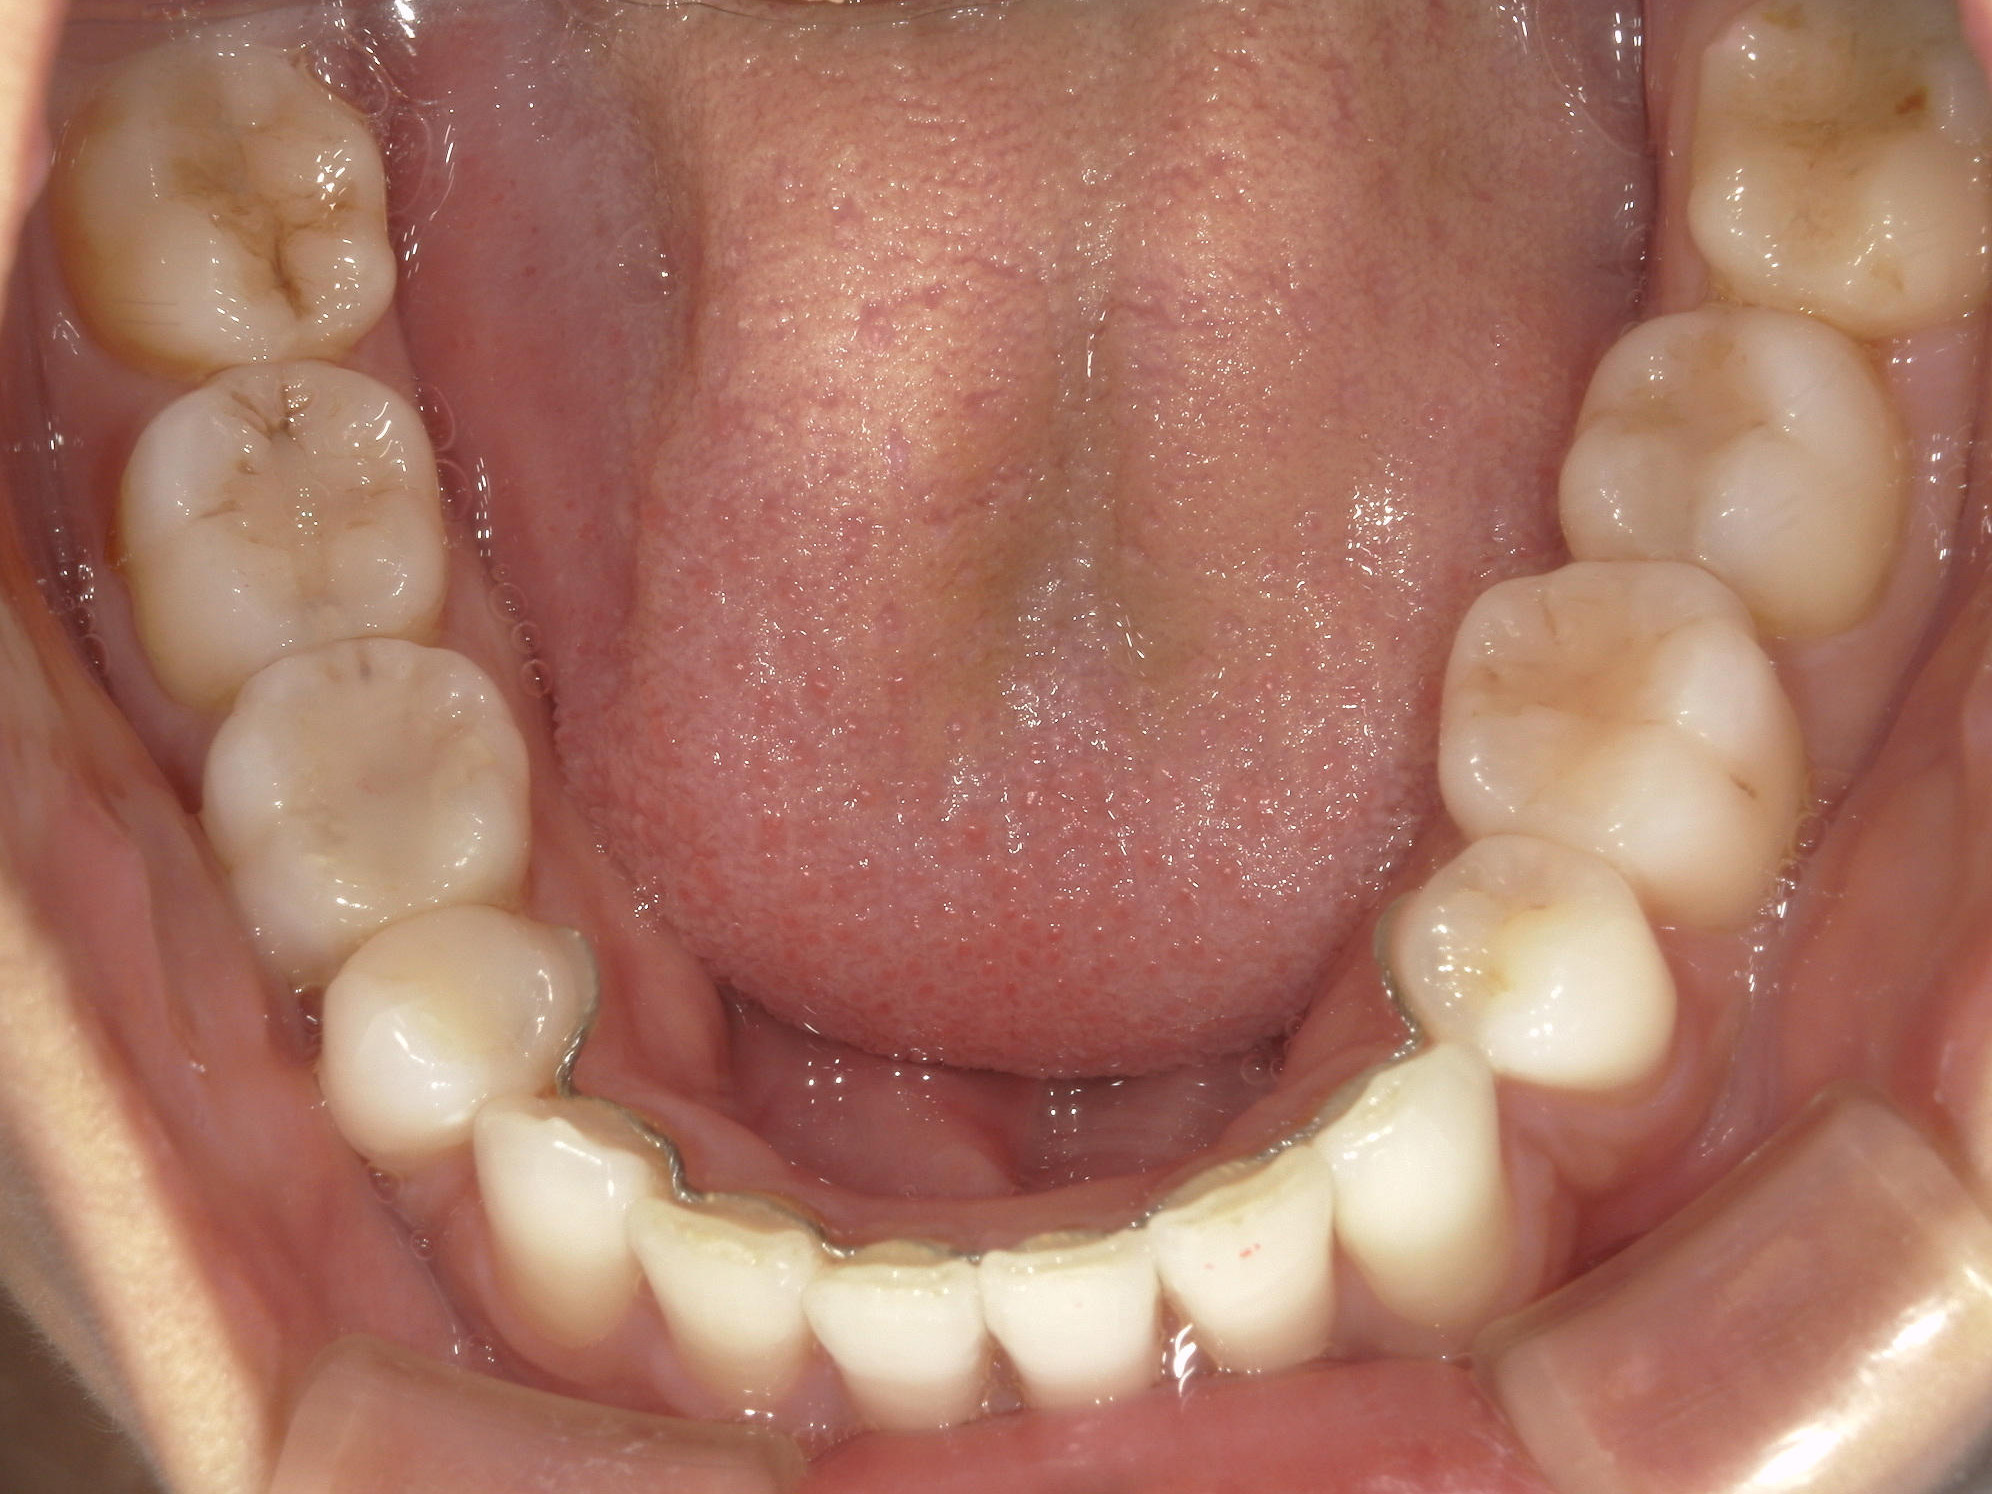

全顎ワイヤー矯正 症例(82)

主訴: 前歯の歯並びが気になる。

上下左右 第一小臼歯(4本)、左右上 親不知(2本)を抜歯。

ミニインプラント、アップライトスプリングを併用。

矯正前に左右上前歯4本を仮歯に変え、矯正治療後にセラミック(SHT)に冠せなおしました。

カテゴリー : ガタガタ(叢生)